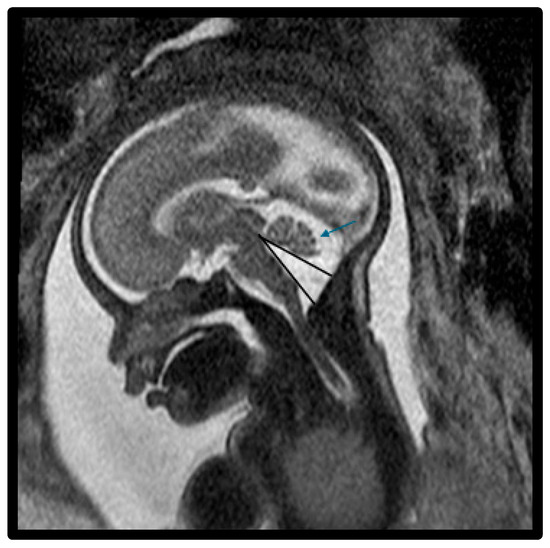

| Vermis AP (mm) * | 10.8 ± 6.2 (n = 6) | 11.8 ± 3.0 | 14.8 (SD, 3.3) | 0.002 |

| TVA (°) * | 93.7° ± 18.1° (n = 6) | 50.9° ± 17.3° | 21.7° (SD, 15.5°) | <0.001 |

| Enlarged CM * | 7/7 (100%) | 7/14 (50%) | 3/6 (50%) | 0.002 |